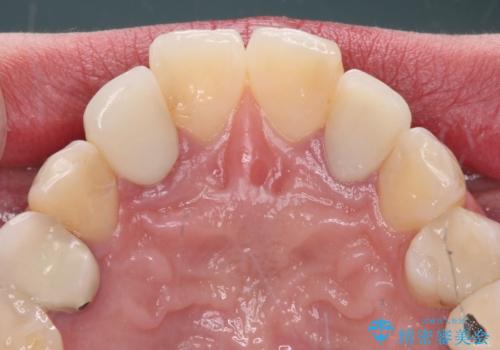

- クラウンから金属の土台が見えてきてしまったとのことで、作り替えを希望して来院された患者様です。

前歯や金属が露出している歯、痛みを感じる歯を中心に、オールセラミッククラウンにて補綴治療することとしました。

以前はセラミッククラウンのフレームとして金属が使用されており、歯肉の経年変化やセラミックのすり減りなどにより、金属が見えるようになってくることがあります。

現在は金属の代わりに強化セラミックを使用したオールセラミッククラウンが主流です。金属色が気になる方はご相談ください。